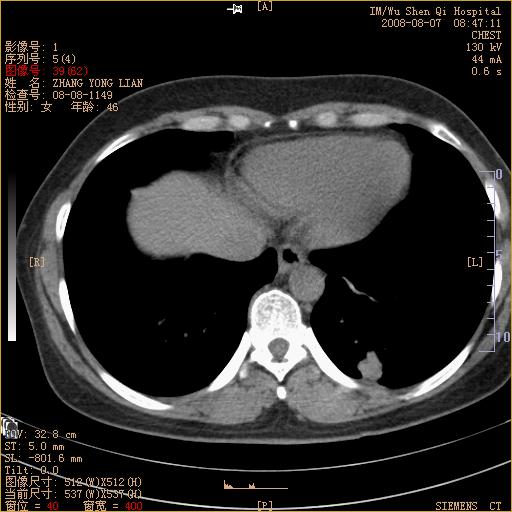

标题: CT15050:女,46岁,咳嗽胸痛一月余 [打印本页]

纵隔窗没发全,左下肺近胸膜处结节。有长毛刺,纵隔淋巴结增大,不排除恶性病变。

考虑左肺下叶后基底段周围型肺癌伴纵隔淋巴结转移可能性大。

左下肺ca并纵隔及左肺门区淋巴结转移。

1)考虑左肺下叶后基底段周围型肺癌伴纵隔淋巴结转移。2)脾内低密度灶,性质待定;不排除转移瘤可能。